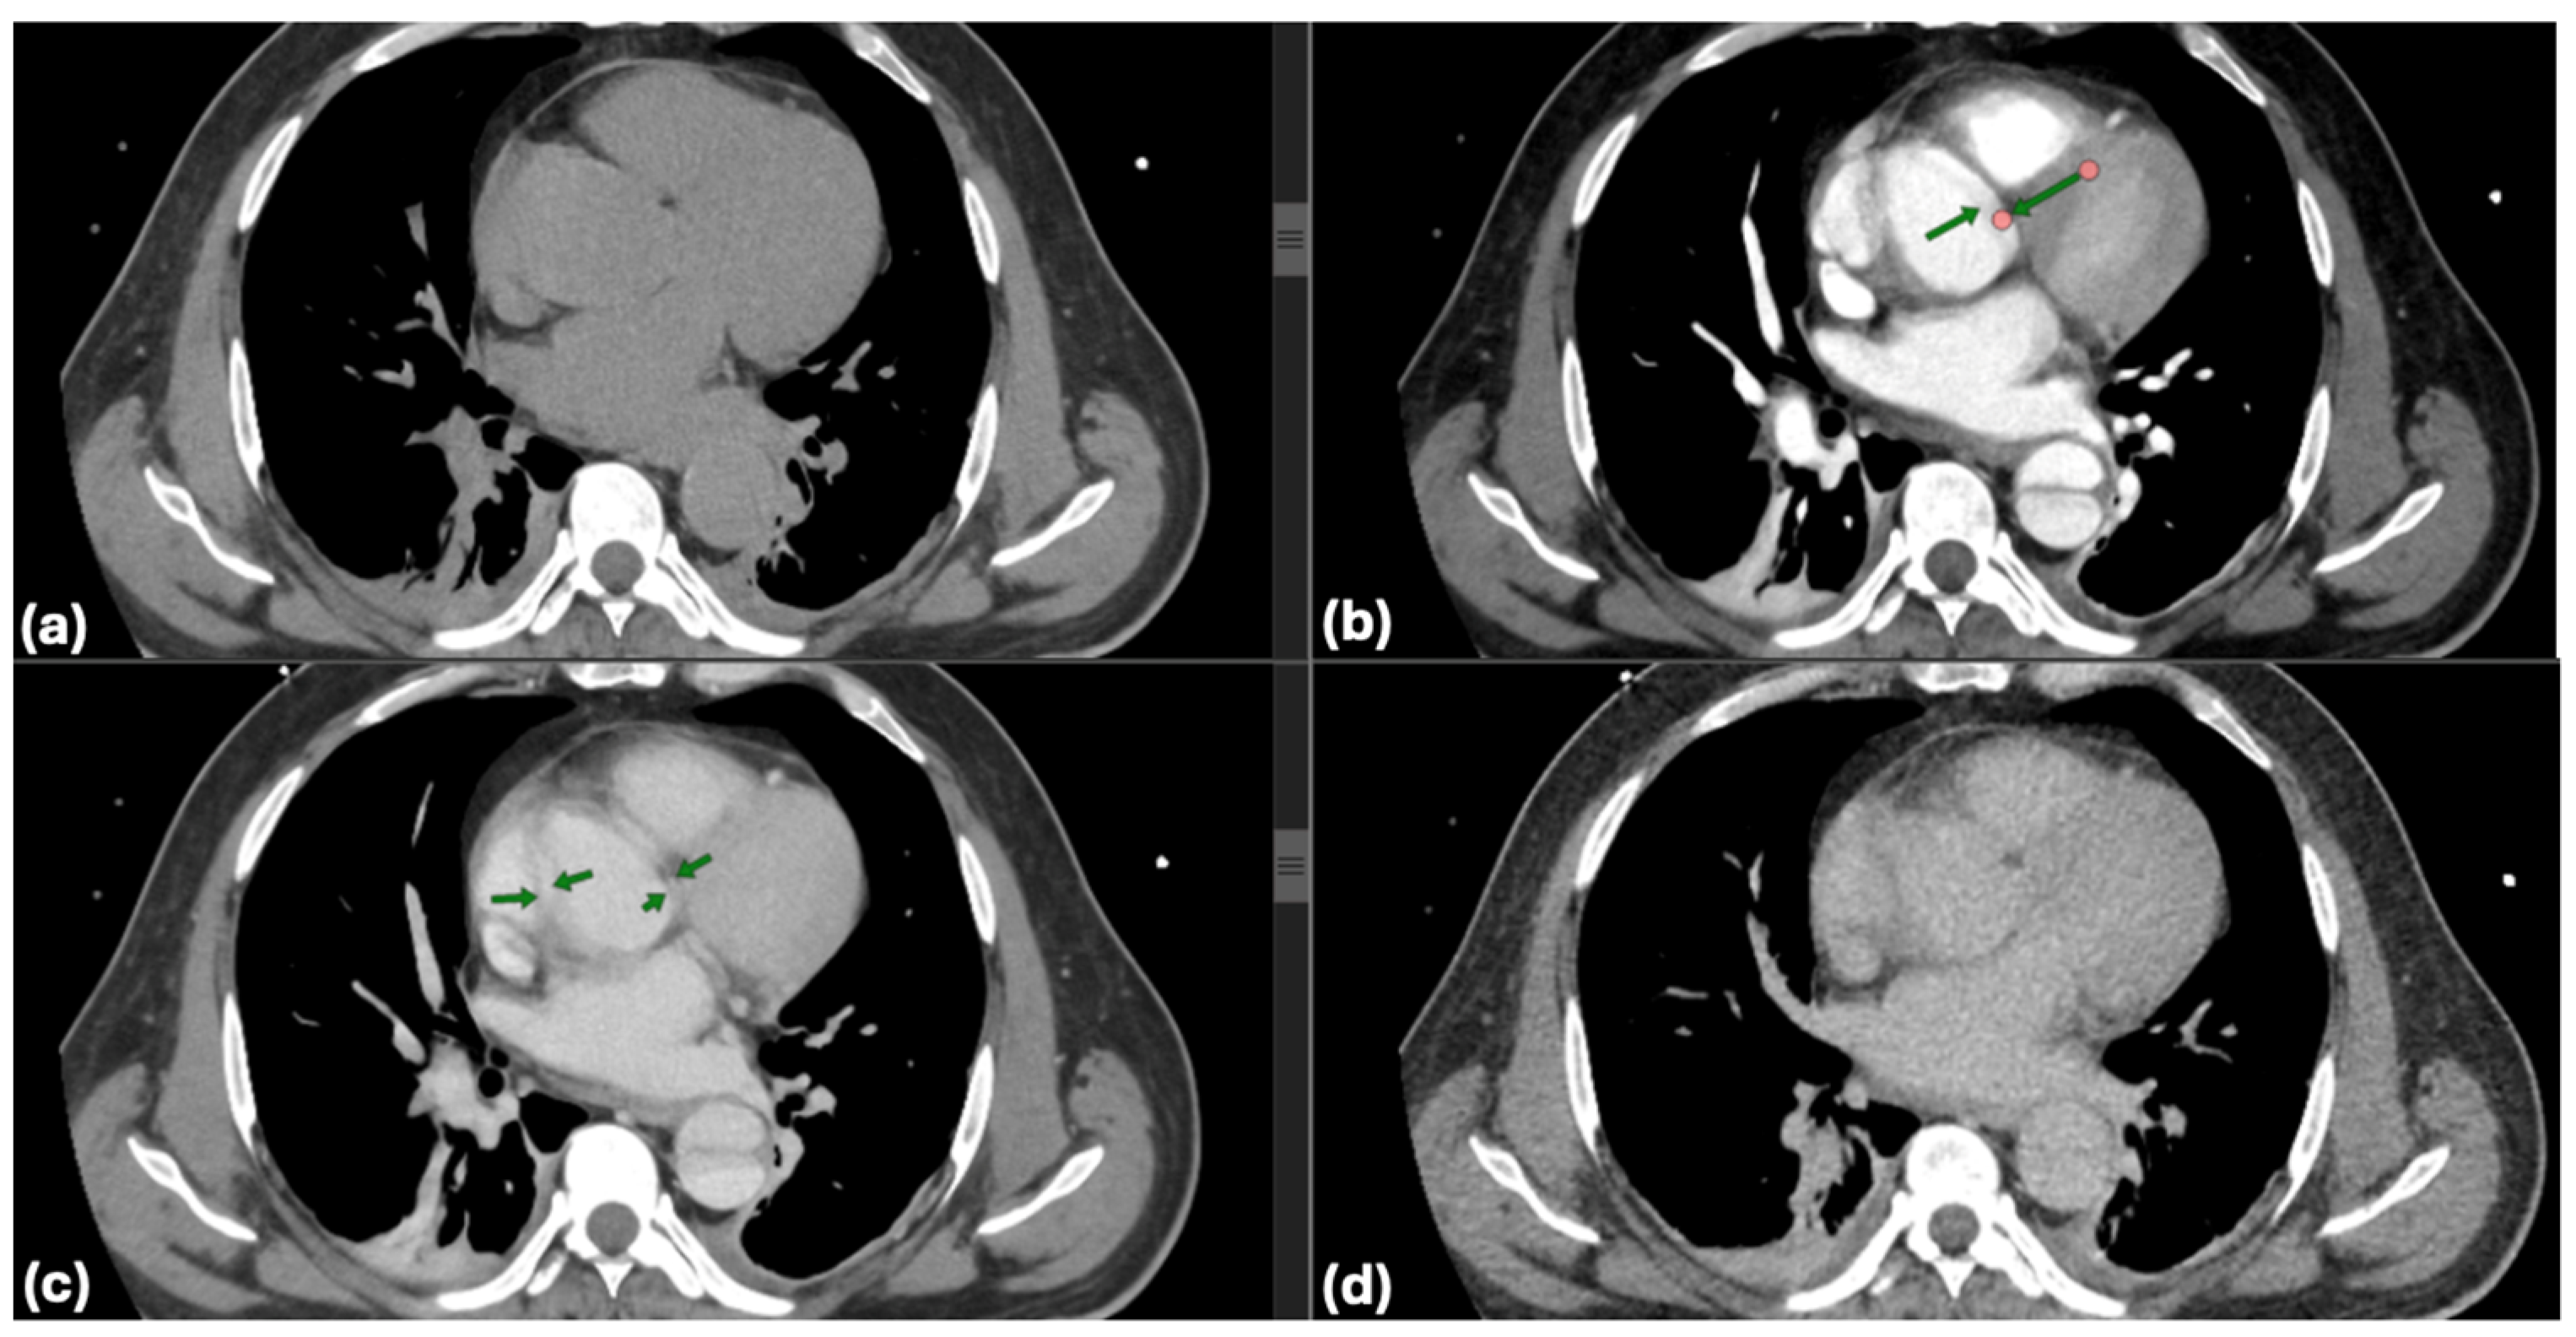

CTA indicated that all cases were associated with Stanford Type A dissections. In 23.1% of patients, dissection extended to the aortic arch, whereas 38.5% exhibited involvement of the descending aorta. Echocardiography results revealed that 26.9% of patients exhibited moderate to severe aortic regurgitation, while 19.2% showed pericardial effusion, thereby heightening the necessity for surgical intervention. The mean LVEF was 56.7%, suggesting that cardiac function was preserved in the majority of patients prior to surgery. Radiological evaluation of Stanford Type A aortic dissections provides essential insights into the pathophysiology and anatomy of the condition. Axial CT sections are particularly valuable in delineating the true and false lumens, as well as the intimal flap that separates them. Figure 5 highlights these features, demonstrating the compressed true lumen and the delayed opacification of the false lumen in the venous phase compared to the arterial phase. Additional findings, such as intimal calcifications, further contribute to a comprehensive understanding of the imaging characteristics of this pathology.

Imaging modalities, especially CTA, were essential for diagnostic and anatomical assessment. In our cohort, CTA findings directly influenced the management pathway in multiple instances. For example, in four cases (15.4%), pericardial effusion detected on imaging necessitated immediate surgical intervention to prevent cardiac tamponade. In nine patients (34.6%), extensive aortic arch involvement observed on CTA dictated the need for total arch replacement. Additionally, imaging findings identified branch vessel involvement in six patients (23.1%), which prompted closer intraoperative vascular assessment to prevent ischemic complications. These findings demonstrate that imaging was not merely a diagnostic tool but also a cornerstone in therapeutic decision-making, shaping both the urgency and extent of surgical intervention. This was exemplified by a representative case of a 57-year-old male with a complex DeBakey Type I dissection (Figure 9 and Figure 10). The case underscores the critical role of advanced imaging in identifying the extent of dissection and guiding timely surgical intervention, which is consistent with our study findings. The detection of aortic regurgitation in 26.9% and pericardial effusion in 19.2% underscores the efficacy of multimodal imaging in identifying problems that require immediate surgical intervention. Outcomes of surgical versus conservative management in our sample reflect findings from IRAD and other registries, revealing in-hospital mortality rates of 12.5% for surgically treated patients compared to 60.0% for those receiving conservative management. The decision between surgical and conservative management was primarily driven by patient stability, comorbidities, and imaging findings. Hemodynamic instability, evidence of rupture, and significant pericardial effusion were immediate surgical indications observed in 61.5% of our cohort. Conversely, conservative management was chosen in patients with advanced age, significant comorbidities, or family refusal of surgical intervention. Despite efforts to stabilize conservatively managed patients with pharmacological blood pressure control and vigilant monitoring, outcomes remained significantly inferior, highlighting the limitations of non-surgical approaches in Stanford Type A dissections. Kaplan–Meier survival studies indicated an 87.5% one-year survival rate for surgical cases against 30% for conservative care, highlighting the critical life-saving effect of prompt surgical intervention [20,21].

Advancements in diagnostic imaging have significantly enhanced the early identification and management of acute Stanford Type A aortic dissections. Methods like CTA and ECG-gated scans have markedly shortened diagnostic delays, facilitating accurate and prompt detection of dissections. The hyperacute nature of aortic dissection presents complications, especially in emergency situations where clinical manifestations may resemble those of myocardial infarction or pulmonary embolism. To tackle these challenges, improved imaging methods and algorithms for differential diagnosis are essential, especially in high-volume emergency facilities, to guarantee that the advantages of contemporary diagnostic equipment result in persistent enhancements in patient outcomes [7,22,27]. The contrast between surgical and conservative management outcomes is further illuminated by the illustrative case, where emergency surgical intervention was necessary to address multi-level vascular involvement and preserve organ function. This case highlights the importance of immediate decision-making and multidisciplinary care, aligning with our cohort results (Figure 11).

Figure 5. Multiphase CT imaging of Stanford Type A aortic dissection: true and false lumen analysis; (ad): axial CT images demonstrating characteristic findings of Stanford type A aortic dissection. Dark green arrow: intimal flap, marking the division between the true and false lumen; red arrow: true aortic lumen, compressed and reduced in size due to the higher pressure within the false lumen; blue arrow: false aortic lumen, which surrounds the true lumen and shows delayed opacification (arterial phase visible (b) versus venous phase in (c)); light green arrow: intimal calcifications within the aortic wall.

Figure 10. CT imaging of Stanford Type A aortic dissection: true and false lumen analysis—transverse sections: (a) compression of the true lumen (purple arrow) by the false lumen (green arrow) within the ascending aorta indicates compromised blood flow, necessitating immediate surgical intervention to restore adequate perfusion; (b) involvement of the descending thoracic aorta shows significant expansion of the false lumen (red arrow), with partial thrombosis and dynamic obstruction impacting distal perfusion (blue arrow). These findings underscored the urgency of surgical repair to prevent ischemic complications.

Figure 11. Three-dimensional reconstruction of Stanford Type A aortic dissection—preoperative planning and postoperative assessment: (a,b) preoperative imaging: the 3D reconstructions display the extensive dissection involving the ascending aorta, aortic arch, and descending thoracic aorta. These images clearly visualize the dissection flap and luminal architecture, aiding in the precise identification of entry and re-entry tears. The preoperative assessment facilitated critical surgical decisions, including the selection of graft size (30 mm Dacron graft) and the extent of aortic arch replacement. Additionally, the reconstructions provided essential insights for planning hypothermic circulatory arrest and cerebral perfusion strategies during surgery.